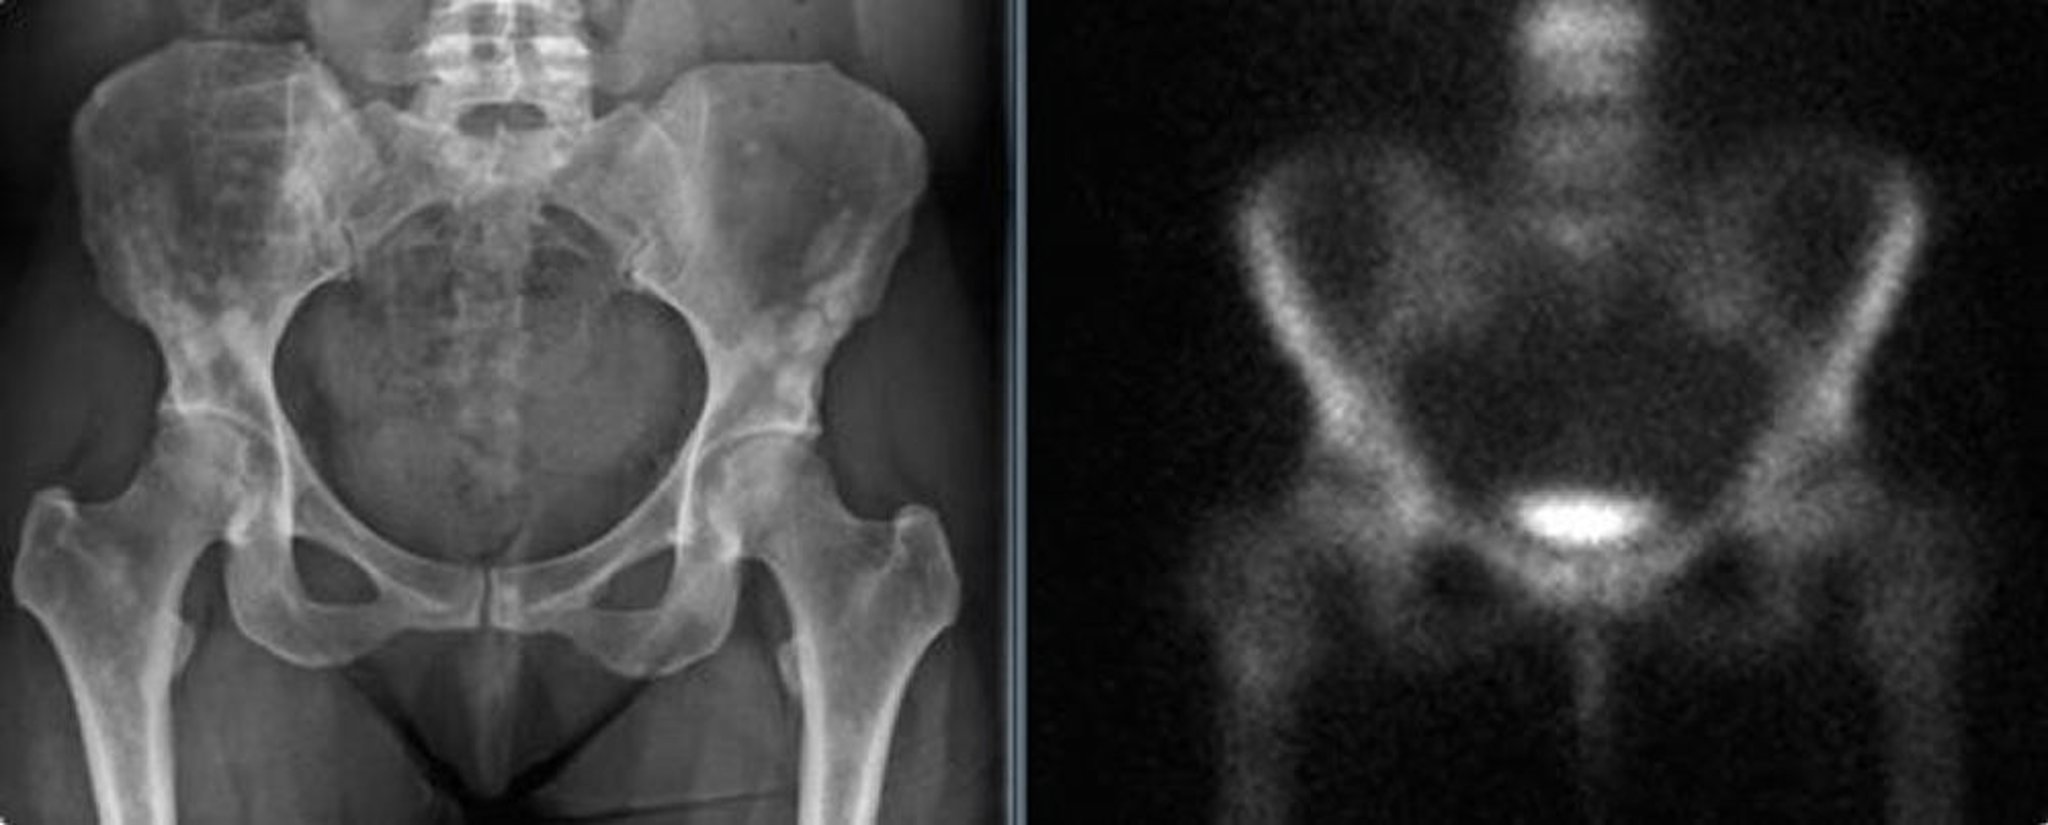

Остеопойкилоз таза

На рентгенограмме таза (слева) виден остеопойкилоз таза у взрослой женщины. Эти уплотнения могут быть ошибочно приняты за бластические метастазы. Сканирование костей (справа) не показывает значительного повышенного захвата.